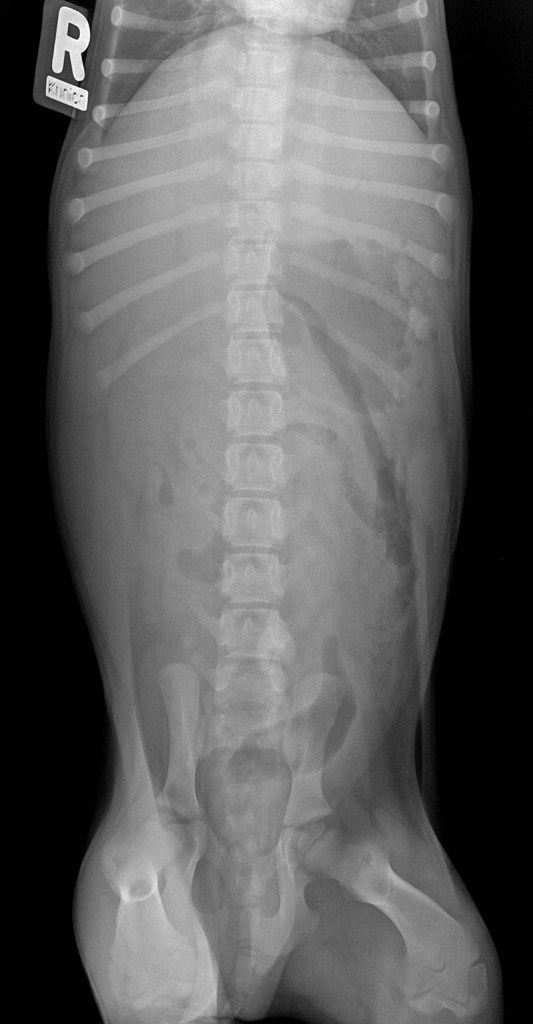

VD_800pix